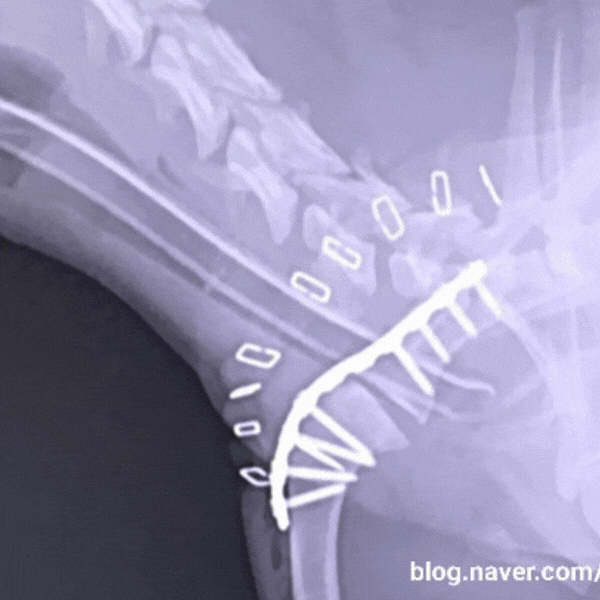

병원에서 진단받은 결과는 어깨 관절 탈구. 처음에는 맞춰 넣고 경과를 보았지만, 반복적으로 탈구가 일어나 결국 수술까지 받게 되었습니다.

수술 후 5개월간 재활과 관리가 필요했고, 그 과정에서 관절 영양제의 중요성을 크게 체감했어요. 특히 연골 세포 재생에 도움을 주는 성분이 포함된 영양제를 꾸준히 급여하면서, 뼈가 점차 회복되는 걸 확인할 수 있었습니다.

놀랍게도 수술 당시 양쪽 슬개골 탈구 2기 진단까지 받았던 도래가 지금은 1기 상태로 호전되어 유지 관리 중입니다.